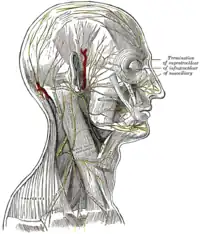

Nervii scalpului, feței și părții laterale a gâtului.